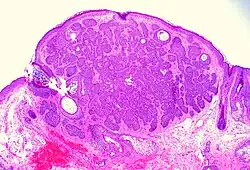

Basal-cell carcinoma can broadly be divided into three groups, based on the growth patterns.

- Superficial basal-cell carcinoma, formerly referred to as in-situ basal-cell carcinoma, is characterized by a superficial proliferation of neoplastic basal-cells. This tumor is generally responsive to topical chemotherapy, such as imiquimod, or fluorouracil, although surgical treatment is better able to ensure complete removal and confirm that there is not an underlying more aggressive subtype that was not sampled in the initial biopsy.

- Infiltrative basal-cell carcinoma, which also encompasses morpheaform and micronodular basal-cell cancer, is more difficult to treat with conservative methods, given its tendency to penetrate into deeper layers of the skin.

- Nodular basal-cell carcinoma includes most of the remaining categories of basal-cell cancer. It is not unusual to encounter heterogeneous morphologic features within the same tumor.